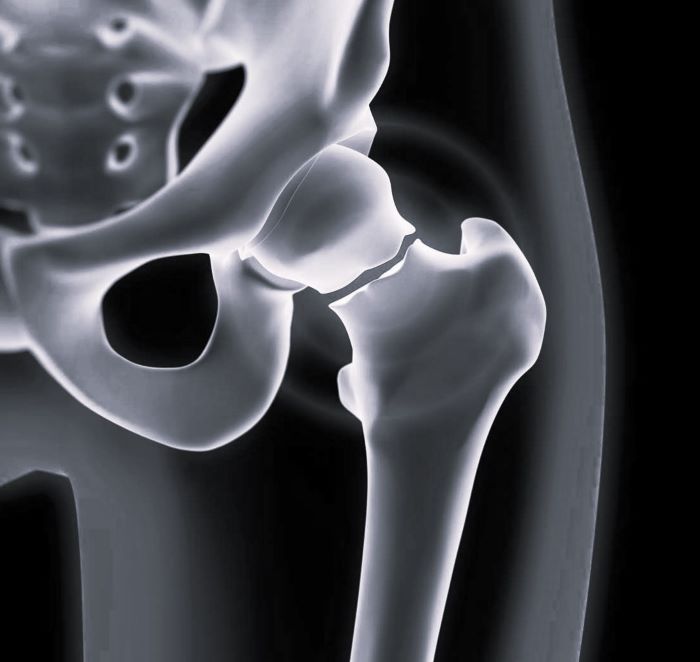

Перелом Бедра Фото Рентген

Перелом Бедра Фото Рентген 138 фото